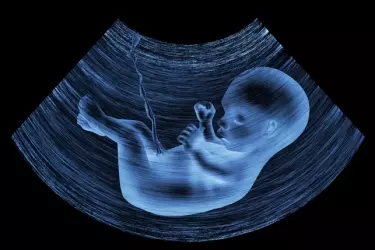

Ultrasound involves the use of high-frequency sound waves to create images of organs and systems within the body. An ultrasound machine creates images that allows various organs in the body to be examined. The machine sends out high-frequency sound waves, which reflect off body structures. The transducer has receptors which receive these signals and convert them into digital signals and form image of the body organ on the computer screen. Ultrasound is the gold standard for looking at the health of foetus in pregnant women. It allows the gynaecologists to detect any congenital abnormalties in the foetus and take corrective action.

Pregnancy Ultrasound - In order to measure the growth of the foetus, ultrasound is the only diagnostic modality. During the nine months of the pregancy atleast 3 ultrasound exams are done, one in every trimester. In the first ultrasound of the pregnancy the viability of the foetus is determined alongwith foetal heart rate and the gestational age. This ultrasound also gives the expected date of delivery.